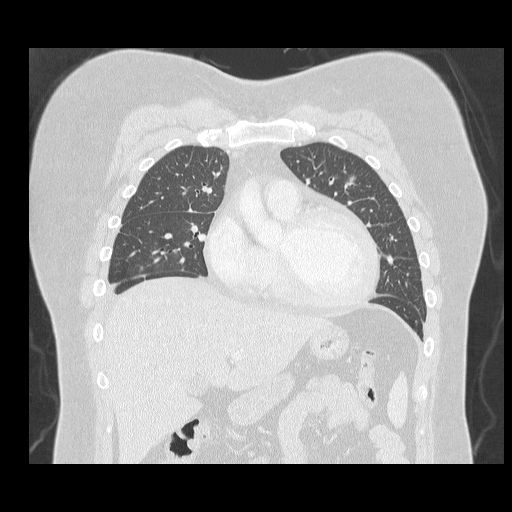

오랫동안 고혈압을 가지고 계셨지만 관리하지 않으셔서 심부전(심장기능저하)가 나타난 환자분 심장초음파 결과